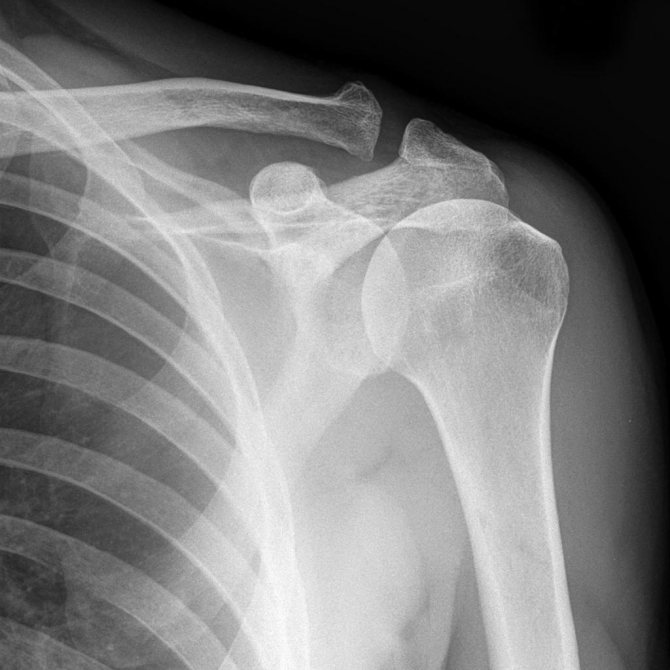

Наиболее распространенные патологии плечевого сустава

Все патологические изменения фиксируются врачом в заключении. Снимки являются основой для постановки диагноза. Просвечивая плечевой сустав на рентгене, выявляют следующие патологии:

- Передний вывих плеча – наиболее распространенное структурное нарушение, встречается в 98 % случаев.

- Задние вывихи диагностируются редко

- Вывих с переломом шейки плечевой кости.

- Застарелый вывих. Такие патологии тяжело поддаются терапии. на мягких тканях образуются рубцы, меняется тонус мышц, развивается дегенеративный процесс мышечной ткани.

- Травмы ротаторной манжетки.

- Артрозы.

- Артриты.

- Остеофиты, характеризующиеся уплотнением капсулы и образованием в ней кальцинатов (отложение солей кальция).

- Остеопороз чаще диагностируется у людей пожилого возраста.